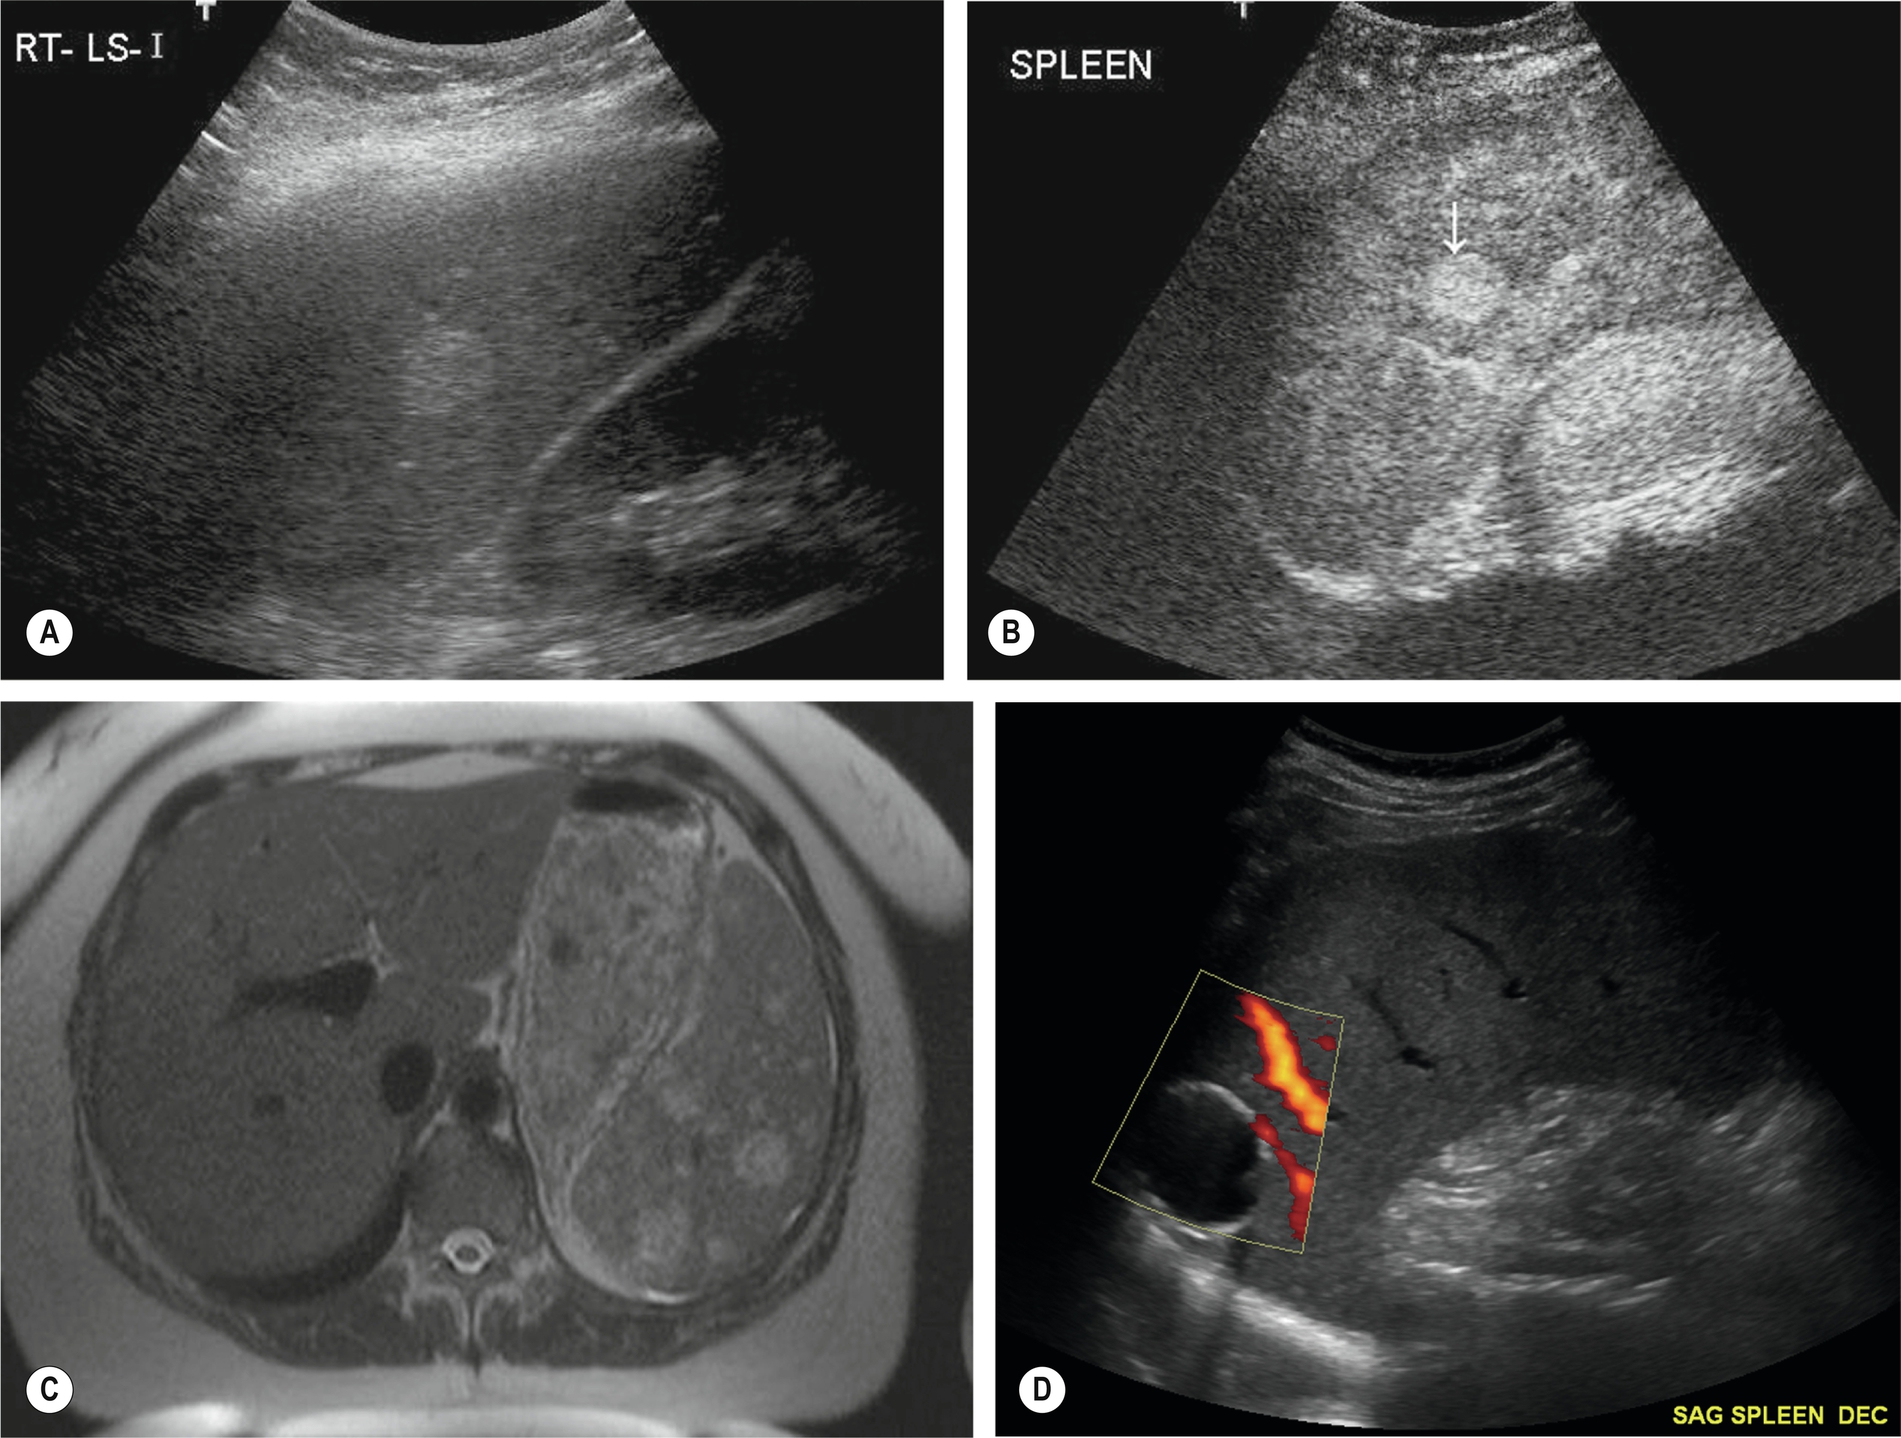

Initially, the area of infarction is hypoechoic and usually wedge-shaped, solitary, and extending to the periphery of the spleen (Fig. 5.7). In the acute phase of infarction, B-mode ultrasound is not often useful, only identifying 50% of infarctions resulting in a high false-negative rate. The lesion may decrease in time and gradually fibrose, becoming hyperechoic. If the infarction is large, it may demonstrate reduced Doppler perfusion when compared to the normal splenic tissue, and CEUS may be particularly helpful in outlining the area of non-perfusion, allowing a definitive diagnosis and is represented as a triangular or slightly rounded area with the base extending to the splenic capsule. In rare cases of total splenic infarction (Fig. 5.7D), because of occlusion of the proximal main splenic artery, gray-scale sonographic appearances may be normal in the early stages.

As lymphatic drainage is by one-directional flow back toward the heart, it is necessary to consider this when looking for spread from a known malignancy. Lymphatic circulation from the visceral organs will drain into the nodes between the lungs and around the intestines, and so this is often where the first evidence of malignant spread is seen. This lymphatic drainage will continue either along the right lymphatic duct or the thoracic duct (left side) and then enter the bloodstream via the subclavian veins in the neck, Palpable lymphadenopathy in the supraclavicular fossa may be identified in patients with a malignancy and there is evidence of metastatic spread via the lymphatic system (Fig. 5.9A–B).

Normal lymph nodes are difficult to demonstrate on ultrasound, but in certain areas, such as at the porta hepatis, normal lymph nodes can be demonstrated using a suitable acoustic window, such as the liver (Fig. 5.9C), particularly in young and/or thin patients.

A normal lymph node is “bean” shaped and has a smooth, well defined capsule. Because of the tendency of abnormal nodes to be rounder in shape, lymph nodes should be measured at the narrowest point (short axis diameter). Although there can be some variation, a short axis measurement of greater than 10 mm would be considered abnormal. Reactive nodes can sometimes have a more lobular outline and can also be enlarged; clinical context is often useful in these cases. On ultrasound, the cortex of the normal lymph node is mildly hypoechoic with a hyperechoic central hilum which contains the lymphatic vessels and blood supply. This may be clearly seen in superficial nodes, but in deeper positions, the resolution may not be adequate. In these cases, the size and shape of the nodes will be the most important factors to determine abnormality. The search for lymphadenopathy should include the para-aortic and para-caval regions, the splanchnic vessels and epigastric regions, and the renal hilar (Fig. 5.9D–F). Ultrasound has a low sensitivity for demonstrating lymphadenopathy in the retroperitoneum, as bowel contents frequently obscure the relevant areas. CT and MRI can better define the extent of lymphadenopathy, particularly in the pelvis. PET is now commonly used to look for widespread lymphadenopathy.

Enlarged nodes are most often hypoechoic, rounded, or oval in shape and well defined in some cases infiltrating into adjacent structures or may combine to form large, lobulated masses. Nodes must be differentiated from other masses (such as gastrointestinal tract or other inflammatory masses), and Doppler is helpful here. Larger nodes display color or power Doppler radiating from a central hilum.

These are uncommon congenital malformations of the lymphatic system, which are usually diagnosed in the neonatal period or on prenatal sonography. They are predominantly cystic, frequently septated, and may be large (Fig. 5.10). They can compress adjacent organs and vessels, and their severity depends largely upon their location. They are most common in the neck (cystic hygroma) but can be found in various locations, including the abdomen,20 and are occasionally found in adults after a long asymptomatic period.